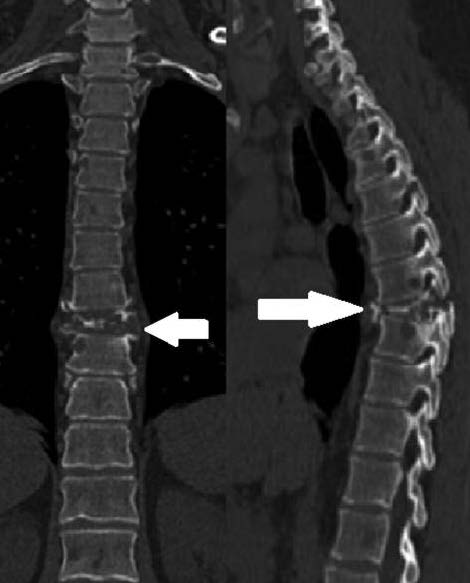

В 2018 г. выполнена КТ грудной полости по поводу воспалительного процесса в легких. Видимые в зоне сканирования кости испещрены очагами деструкции. Размеры и структура образований в переднем отрезке II ребра справа, в паравертебральных отделах слева от компримированного VIII грудного позвонка сохранялись прежними (рис. 3). Участок деструкции в правом поперечном отростке и полудужке I грудного позвонка склерозировался, уменьшился в размерах.

Рис. 3. Компьютерная томограмма грудной полости (2018 г.): распространенный остеодеструктивный процесс в костях.

При КТ отмечалось дальнейшее увеличение количества и размеров ранее существовавших очагов деструкции в костях. Появился новый компрессионный перелом тела I поясничного позвонка. Структура и размеры образований переднего отрезка II ребра справа и паравертебрального образования слева от VIII грудного позвонка и правого поперечного отростка и полудужки тела I грудного позвонка – без динамики.